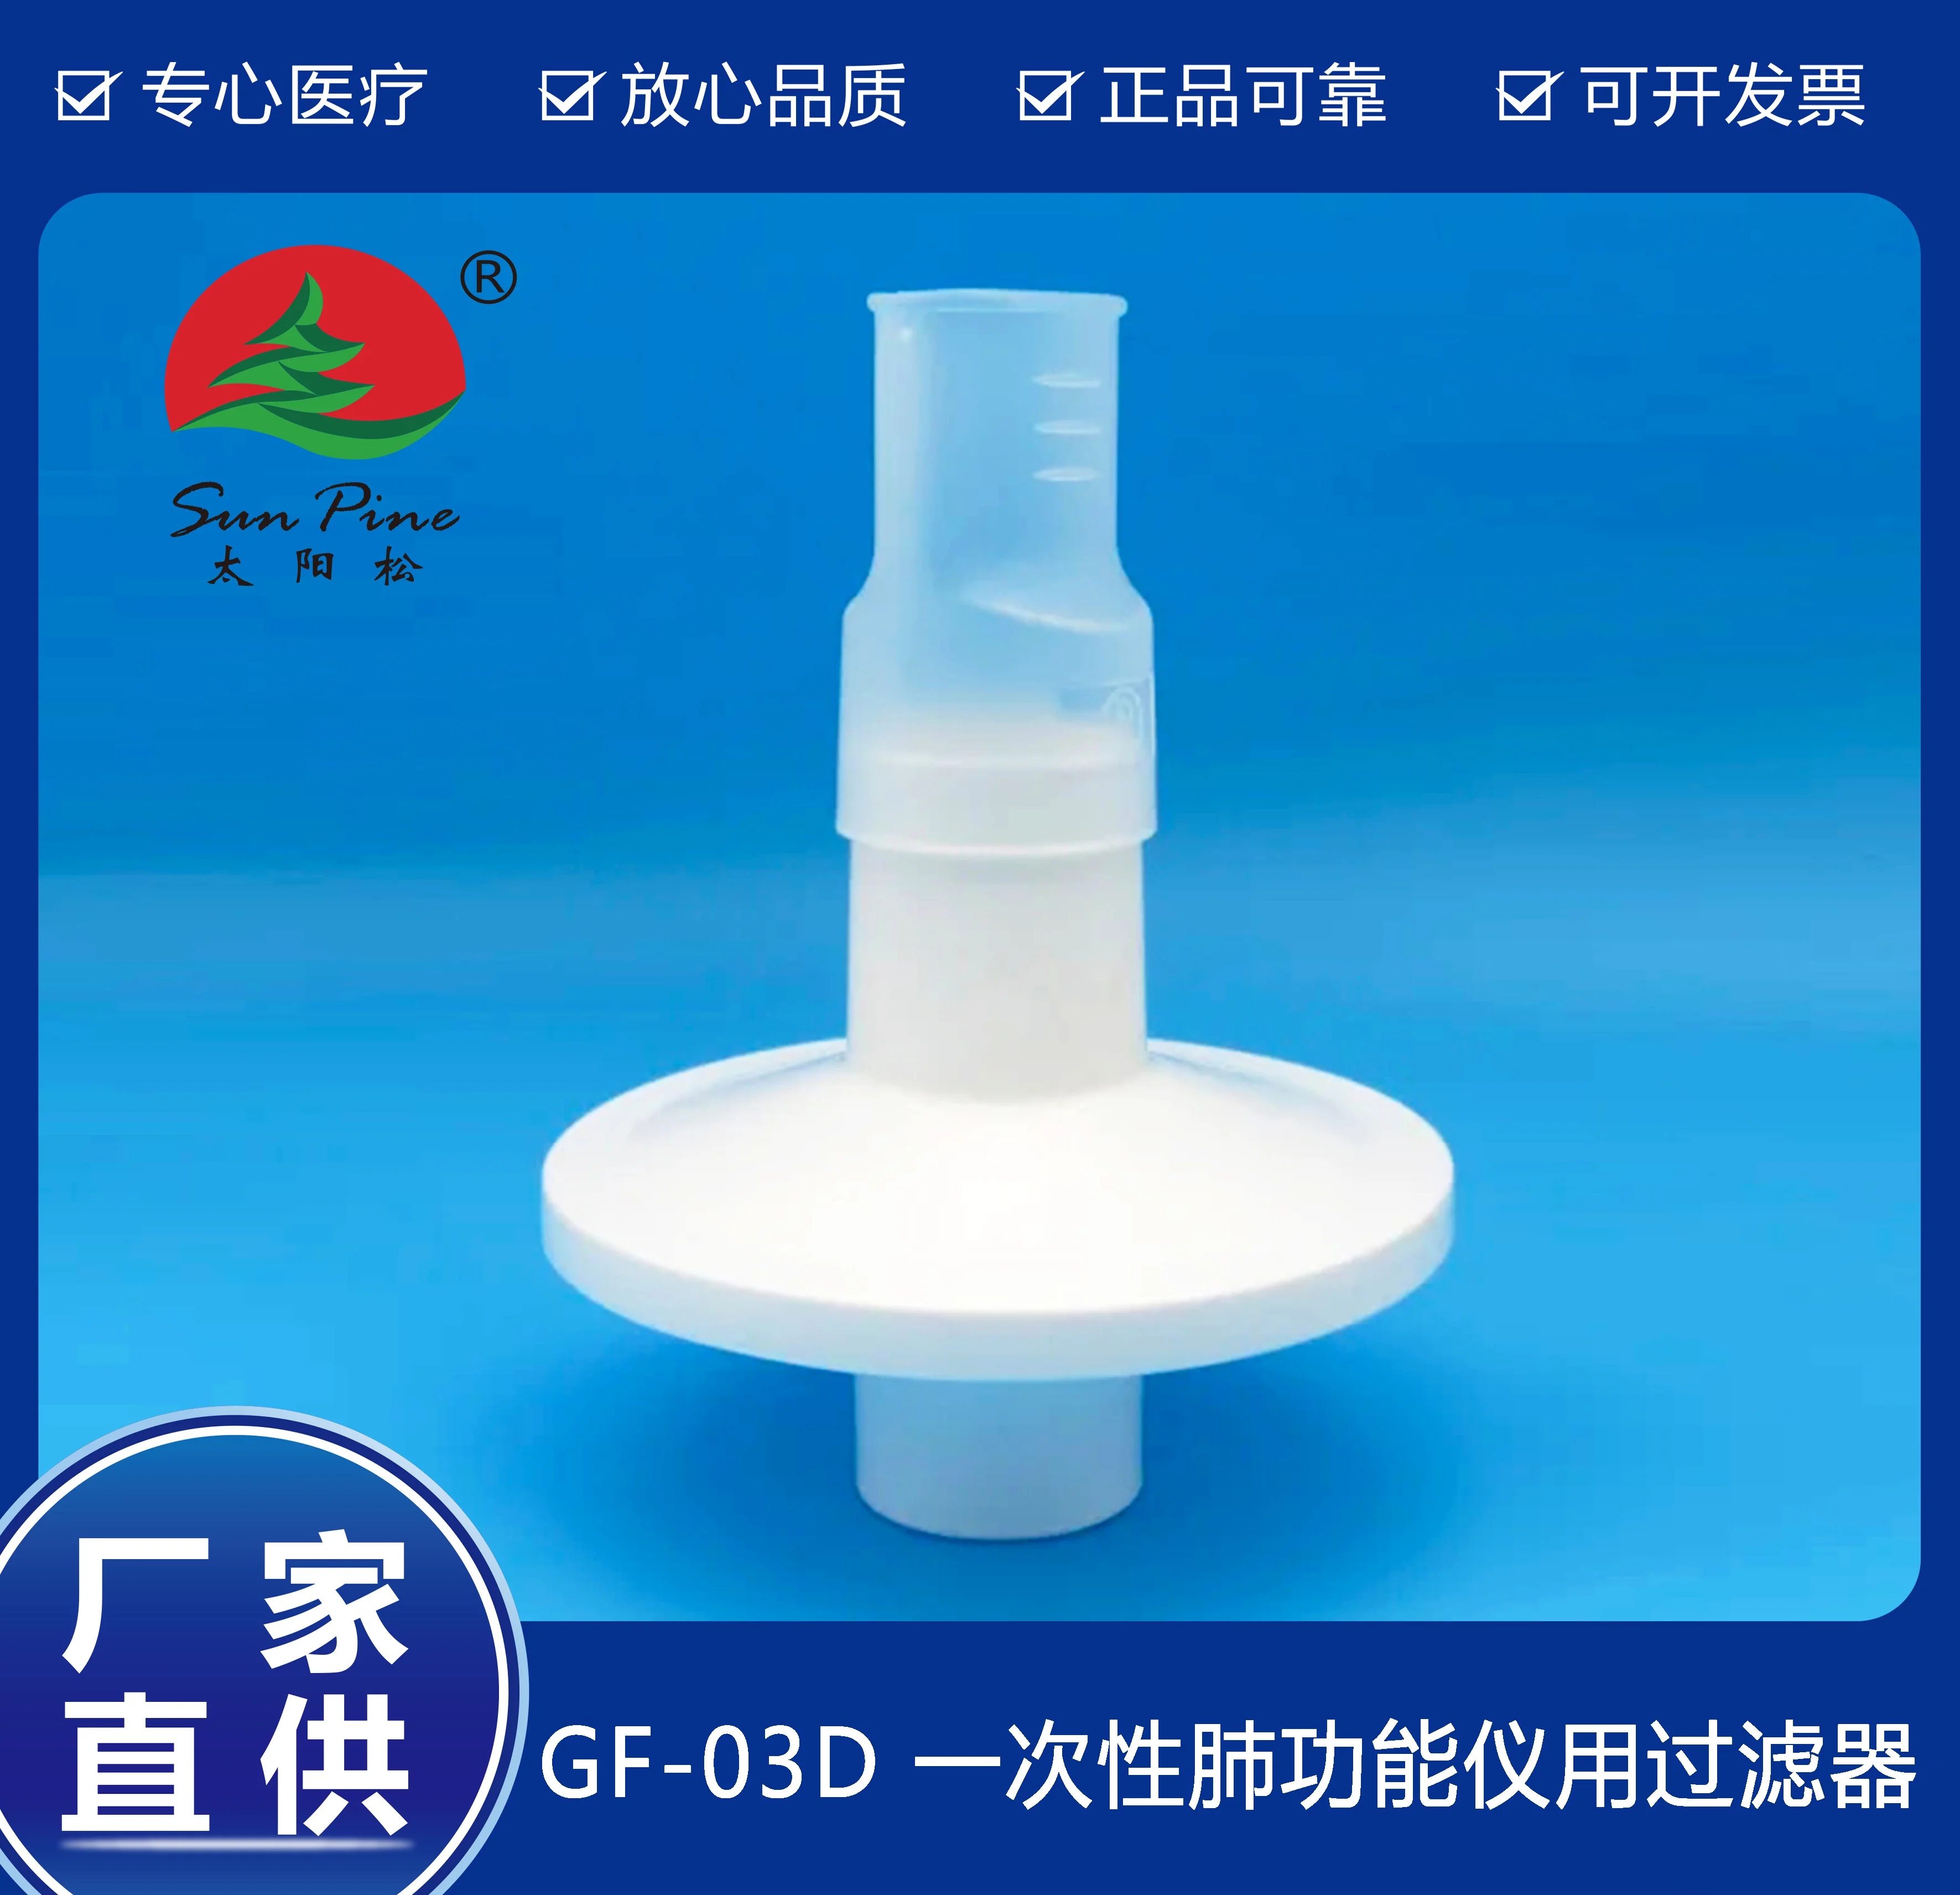

中山高榮電子科技有限公司是一家集自主研制,生產(chǎn)和銷(xiāo)售一體的高新技術(shù)醫(yī)療器械生產(chǎn)企業(yè),嚴(yán)格按照CFDA認(rèn)證,遵守國(guó)家醫(yī)療器械法規(guī)建立了完善的質(zhì)量管理體系,確保提供給客戶(hù)的醫(yī)療器械產(chǎn)品安全健康。公司擁有十萬(wàn)級(jí)、萬(wàn)級(jí)潔凈生產(chǎn)車(chē)間,環(huán)氧乙烷滅菌車(chē)間,有專(zhuān)門(mén)的物理實(shí)驗(yàn)室、理化實(shí)驗(yàn)室和微生物實(shí)驗(yàn)室以及醫(yī)電研發(fā)室、醫(yī)電生產(chǎn)車(chē)間。主要產(chǎn)品有:“太陽(yáng)松”品牌:一次性使用呼吸過(guò)濾器,一次性肺功能儀用過(guò)濾器,咬嘴;“凱華”品牌:醫(yī)用電子產(chǎn)品,肺功能檢查儀等,其中過(guò)濾器,咬嘴可匹配市場(chǎng)上各種不同品牌型號(hào)的肺功能儀使用,可以降低患者吸入或呼出顆粒性物質(zhì)的數(shù)量,防止污染儀器,大限度保障每位受測(cè)者健康安全.